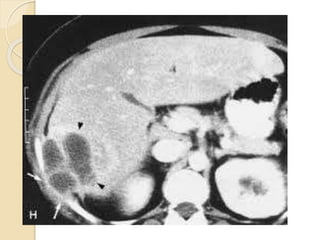

CT ABDOMEN: Mildly enlargedliver with multiple variable sized marginally enhanced cystic lesions are seen scattered in both liver lobes and caudate lobe . the largest measures about 3.5 cm in diameter and located in medial segment of the left liver lobe…… signs cobe with multiple liver granulomas Normal enhancement of the main portal vein and its two main branches. No dilated intra-hepatic biliary

abdominal CT a contrastenhancing multicystic lesions that can be approached by CT guided needle biopsy and C/S